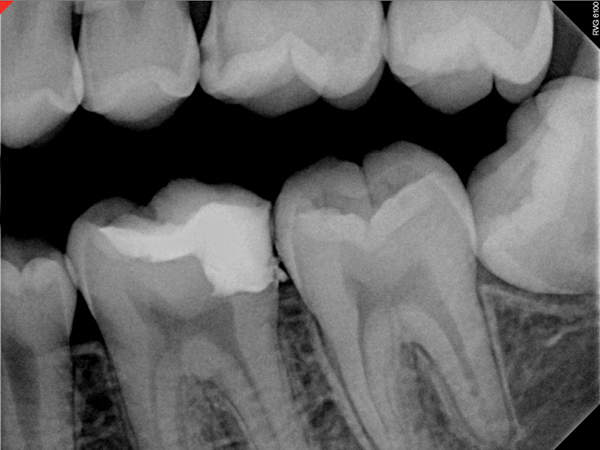

Fig 6. Preoperative radiograph of carious exposure on tooth No. 19. Courtesy of Dr. Mohammed A. Alharbi.

Figure 6

Fig 11. Preoperative radiograph. Courtesy of Dr. Guillaume Jouanny.

Figure 11